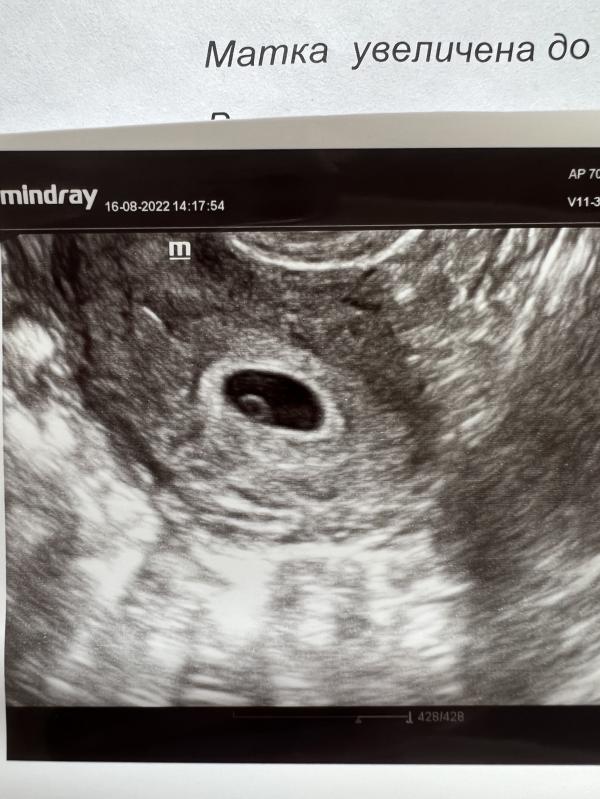

Картина хорошая, никакой угрозы нет

Даже увидела эмбрион 2-3 мм